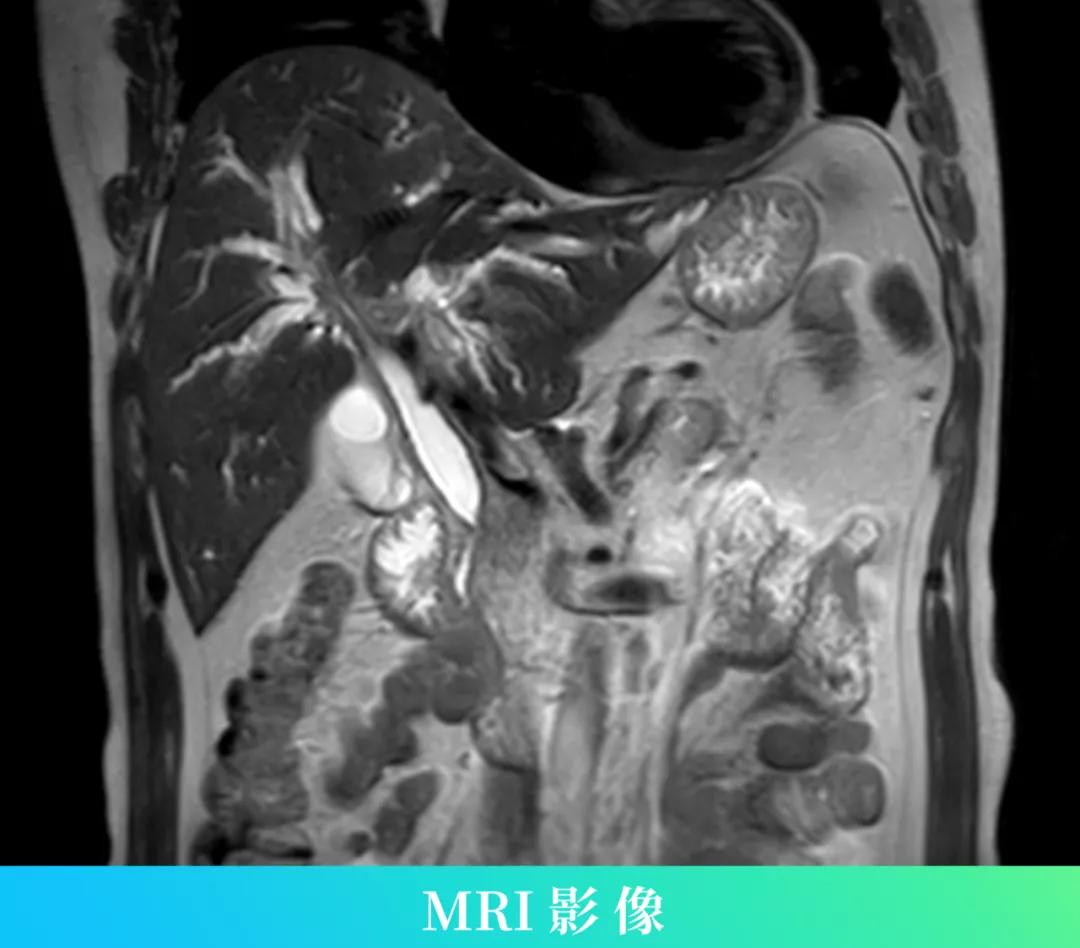

患者治疗前的腹部MRI影像

再次复查了腹部增强核磁和血清免疫球蛋白G4(IgG4)水平,我院核磁结果提示:胰腺肿胀信号异常,近肝门区肝内外胆管、胆总管远段管壁增厚,管腔狭窄,以肝门区肝内外胆管增厚为著,呈跳跃分布,余肝内外胆管迂曲、扩张,考虑免疫相关胰腺炎胆管炎可能大。